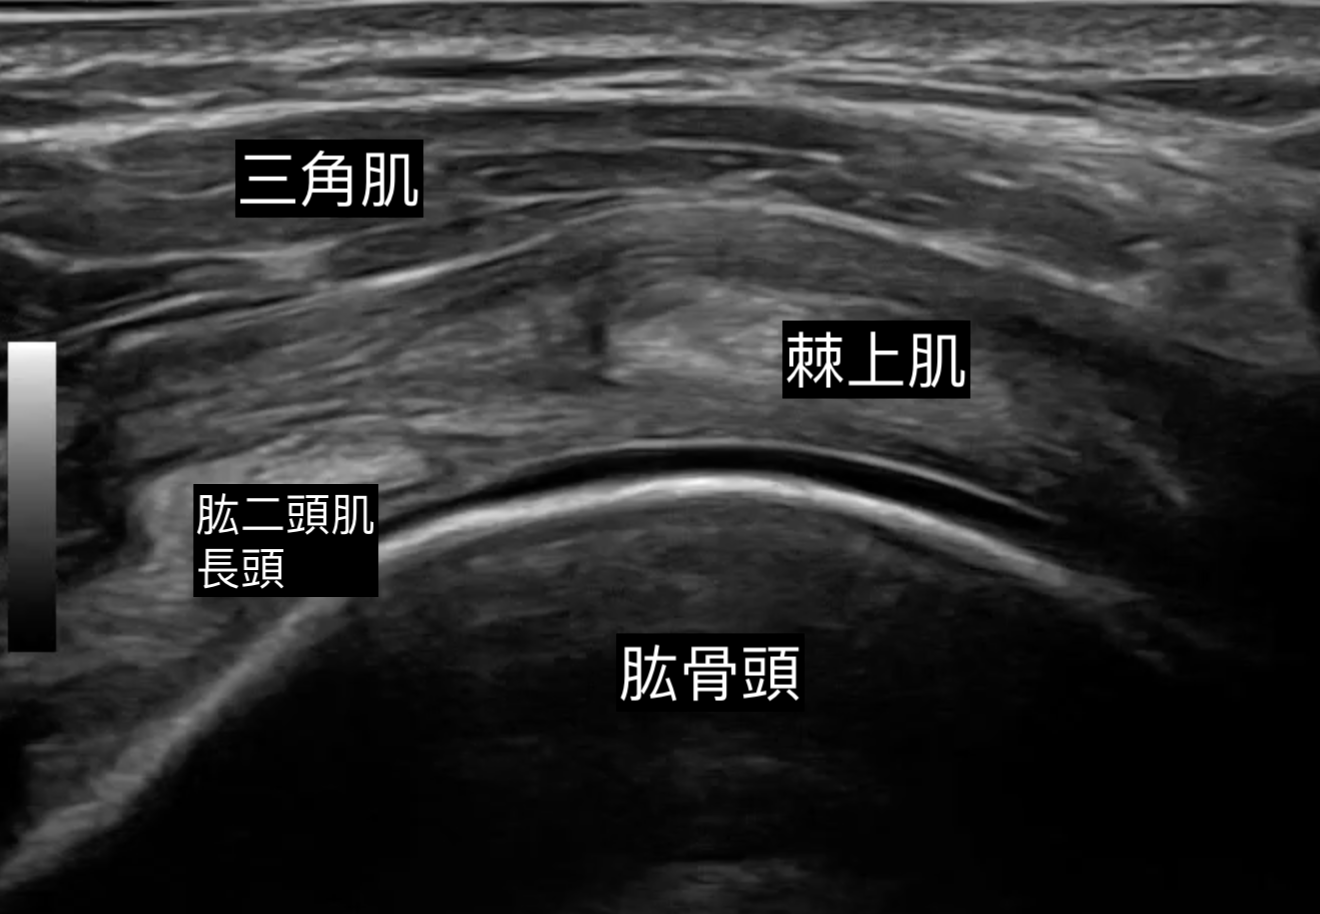

對於受五十肩困擾、一方面保守治療效果未如理想、另一方面不希望做手術的病人,超聲波介入治療提供了一個非手術且高效的解決方案。這項程序結合了影像導航注射與關節囊鬆解,旨在短時間內打破僵硬關節囊的限制。